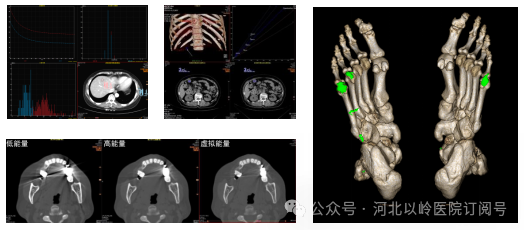

能谱多功能成像

能谱CT突破了传统CT的等密度病灶局限,可形成直接反应病灶组织成分的图像,能够带来更丰富、精准、定量的多参数成像信息,对于肿瘤早期病灶发现、痛风石、结石成分分析、神经介入取栓溶栓后造影剂外渗及脑出血的精准鉴别诊断具有独特价值。